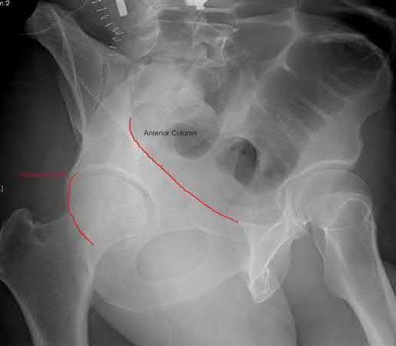

Question 1:

A 35-year-old male is brought to the trauma bay after a severe fall from height. He is hypotensive and tachycardic. An AP pelvis radiograph demonstrates a vertically displaced left hemipelvis with severe disruption of the posterior sacroiliac complex and symphysis pubis. If active arterial hemorrhage is identified on angiography, which vessel is most likely injured in this specific injury pattern?

Correct Answer: Superior gluteal artery

Explanation:

Vertical shear pelvic fractures involve massive disruption of the posterior pelvic ring, including the sacrotuberous and sacrospinous ligaments. The superior gluteal artery exits the pelvis through the greater sciatic notch in close proximity to the sacroiliac joint and is the most commonly injured artery in vertical shear pelvic fractures. In contrast, APC (Anteroposterior Compression) injuries are more typically associated with injuries to the internal pudendal and obturator arteries.